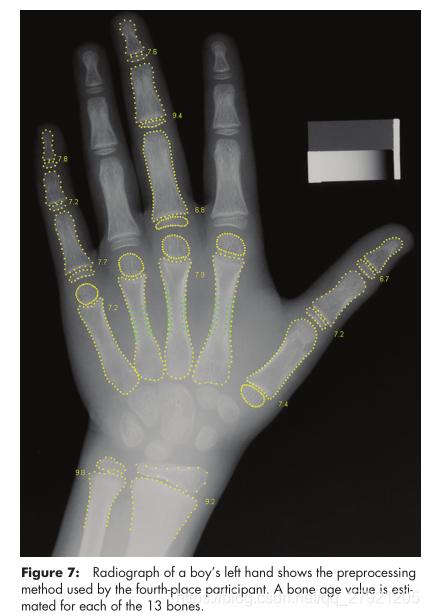

第四名: Hans Henrik Thodberg-MAD=4.505

使用了传统机器学习的方法:使用图像预处理,分割成15块骨头区域,使用传统方法获取特征:骨头形状,生长区的强度模式,生长区的gabor纹理特征。